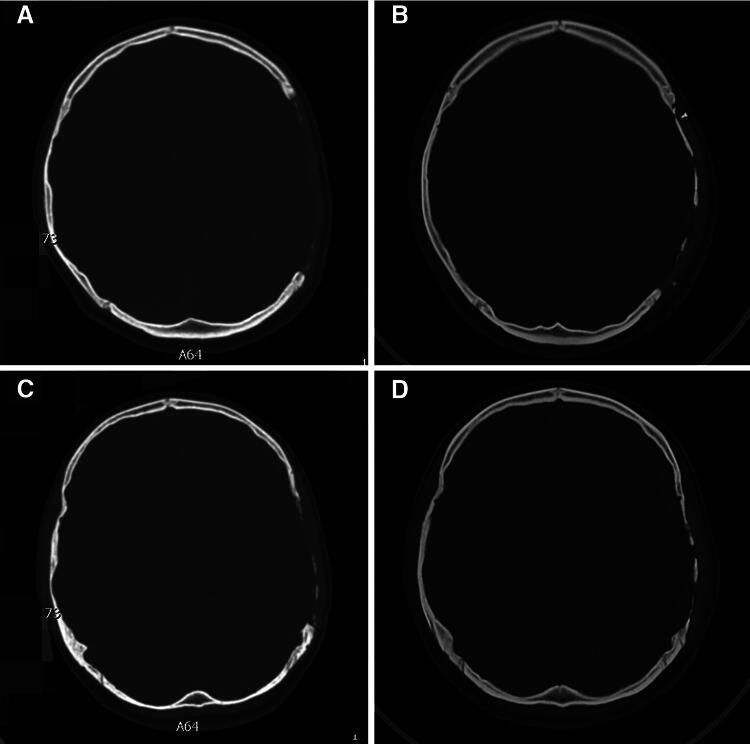

This study aimed to explore the experience and complications of cranioplasty (CP) with polyether ether ketone (PEEK) in pediatric and adolescent patients after decompressive craniectomy (DC). A total of 62 children (aged <18 years) with cranial bone defects due to DC underwent CP with a custom-made PEEK at our department between January 2018 and April 2023. The clinical characteristics, radiological features, surgical conditions, postoperative complications, and follow-up results of these patients were analyzed retrospectively. Kaplan-Meier survival analysis and Cox regression were used to analyze data. The age of the patients ranged from 2 to 17 years. The follow-up periods ranged from 12 to 70 months. Six patients experienced subcutaneous fluid accumulation (9.7%), five experienced epidural fluid accumulation (8.1%), and two experienced scalp inflammation (3.2%), which all were cured before discharge. Seven patients experienced bone gap expansion at the interface between the cranial bone and PEEK during follow-up (11.3%). Univariate analysis showed that DC-CP time interval (<3 months) and age were two influencing factors. Multivariate analysis revealed that age was the most important factor (p < 0.005, hazard ratio = 0.250, 95% confidence interval: 0.096-0.652). No reoperation was performed. Medical follow-ups were carried out further. For pediatric patients with cranial defects after DC who receive CP with a custom-made PEEK, two variables including younger age and too short DC-CP time interval may be unfavorable factors, to make patients experience bone gap expansion at the interface between the cranial bone and the PEEK. Additional data should be collected to validate our conclusions.